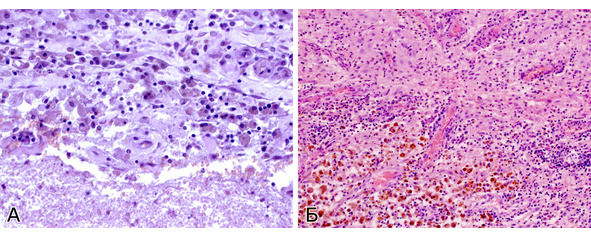

При рутинном исследовании в световом микроскопе (срезы толщиной 5 мкм, окраска гематоксилином и эозином, при необходимости – докрашивание по Ван-Гизон и Маллори) каверномы представляют собой конгломерат тонкостенных полостей разнообразной неправильной формы, выстланных эндотелием и разделенных соединительнотканными перегородками. Соединительная ткань перегородок может быть представлена как тонкими коллагеновыми волокнами, так и грубоволокнистой фиброзной тканью с различной степенью дистрофических изменений. Характерным признаком является отсутствие в стенах каверн гладкомышечных клеток и эластических волокон, а также мозговой ткани между кавернами (рис. 11) (2, 236, 299, 333).

Лишь в отдельных препаратах можно обнаружить незначительные прослойки мозговой ткани. Реактивно измененная мозговая ткань может быть также выявлена вокруг каверн, полностью отделенных, «отшнурованных», от основного конгломерата (рис. 12).

На основании этих признаков проводят дифференциальный диагноз каверном с другими сосудистыми мальформациями, прежде всего, с АВМ, при гистологическом исследовании которых выявляют сосуды артериального и венозного типа с относительно дифференцированными стенками и значительное количество мозговой ткани между ними.

Полости, образующие каверному, могут быть заполнены жидкой кровью либо тромбами в различной стадии формирования (рис. 13).

В ткани КМ могут быть обнаружены участки кальцификации, гиалиноза стенок (рис. 14).

Довольно часто в строме встречаются признаки повторных кровоизлияний в виде остатков гематом различной давности. По периферии каверномы часто можно обнаружить фрагменты капсулы, типичной для хронической гематомы (рис. 15).

Характерной морфологической особенностью кавернозных мальформаций является наличие многочисленных мелких сосудов с кальцинированными стенками в окружающей мозговой ткани (рис. 16).

Рис. 11. Кавернозная мальформация «классического» типа —конгломерат сосудистых полостей различной формы и размеров, выполненных кровью.Ув. х 100

Рис. 12. Отшнуровавшиеся сосудистые полости (1) в ткани мозга с отложениями гемосидерина, гиперплазией глии (2).Ув. х 400

Рис. 13. Тромбоз и склероз сосудистых полостей в «классической» кавернозной мальформации.Ув. х 200

Рис. 14. Кальцификат (стрелка) и склеротические изменения в стенках сосудистых полостей. Ув. х 100

Рис. 15. А. Начальная стадия формирования стенки гематомы – скопления макрофагов, нагруженных гемосидерином. Ув. х 400. Б. Сформировавшаяся капсула гематомыс отложениями гемосидерина, лимфоплазмоцитарной инфильтрацией и новообразованными сосудами. Ув. х 200

Рис. 16. Кальциноз стенок капилляров в прилежащей к кавернозной мальформации ткани мозга (стрелки). Ув. х 200